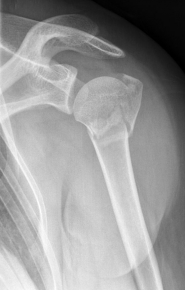

Picture: The subcapital humeral fracture shown here in the axis is not broken and only slightly bruised, so that a conservative therapy is possible. The left image shows the follow-up after 3 weeks. The patient has already started physiotherapy. The x-ray shows an increase bone healing.